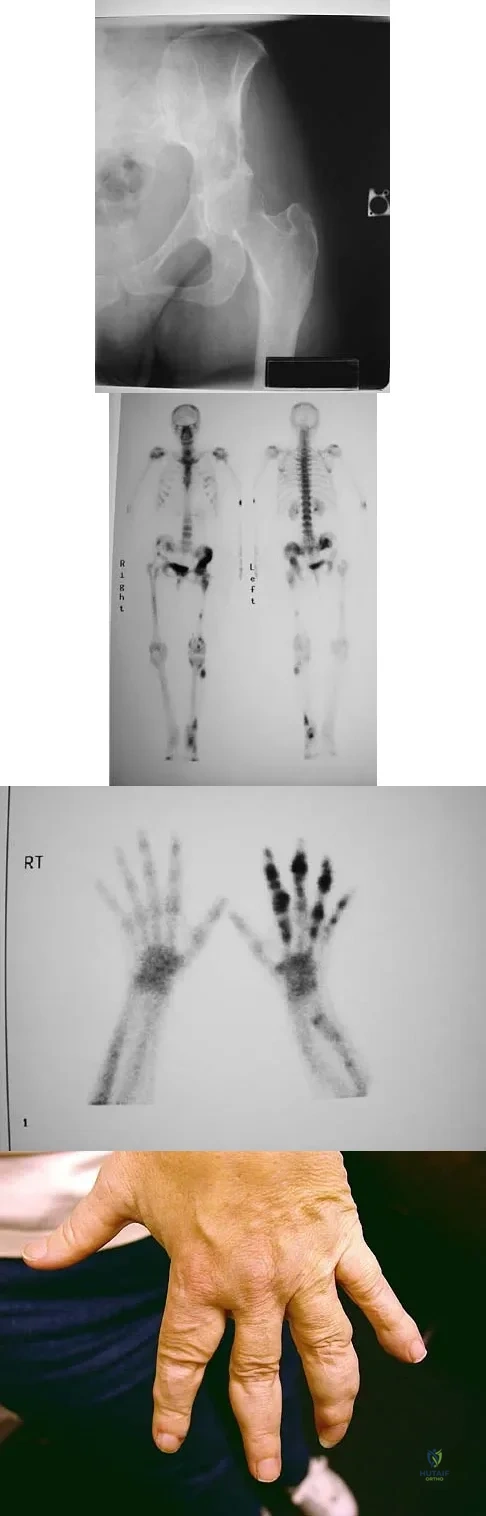

Question 34High Yield

Figure 15a shows the radiograph of a patient who has a chondrosarcoma of the acetabulum. Bone scans are shown in Figures 15b and 15c. Numerous soft subcutaneous masses are present. A clinical photograph of the hand is shown in Figure 15d. What is the most likely diagnosis?

Explanation